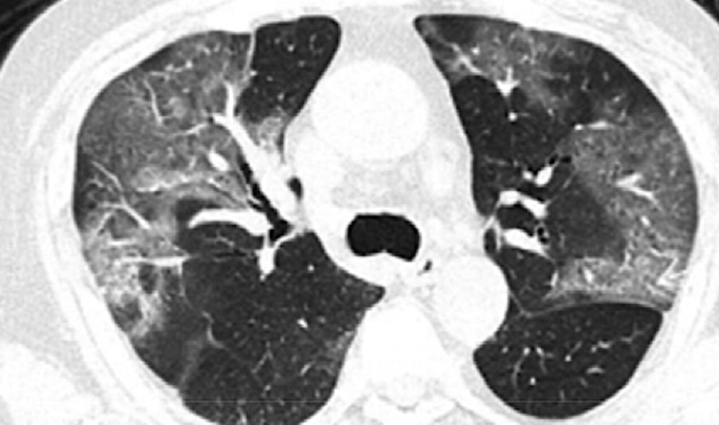

CT란 무엇인가 (속도 중심 검사)

**CT**는 X-ray를 이용해 몸을 빠르게 단면으로 촬영하는 검사입니다.

✔ 대표 사용 상황

- 교통사고 후 출혈 확인

- 뇌출혈 응급 판단

- 폐 질환 (폐렴, 결핵 등)

- 골절 확인